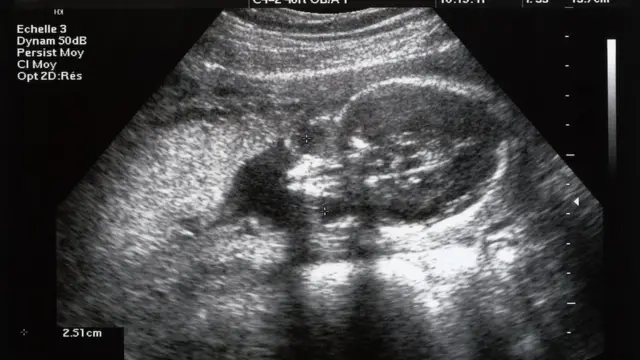

பட மூலாதாரம், Getty Images

தேசிய குடும்ப நல ஆய்வின்படி, தமிழ்நாட்டில், 2015-16ல் 1,000 ஆண் குழந்தைகளுக்கு 954 பெண் குழந்தைகள் இருந்தனர். அதே ஆய்வில் 2020-21ல் 1,000 ஆண் குழந்தைகளுக்கு 878 பெண் குழந்தைகள்தான் உள்ளனர் என்று தெரியவந்துள்ளது. கருவில் இருக்கும் குழந்தையின் பாலினத்தை கண்டறிந்து கருக்கலைப்பு செய்வதால்தான் பெண் குழந்தைகளின் எண்ணிக்கை குறைந்துள்ளதை இந்த புள்ளிவிவரங்கள் காட்டுவதாக குழந்தைகள் நல ஆர்வலர்கள் கூறுகின்றனர்.